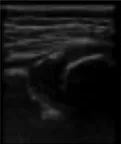

In this study, the weights of each anatomical structure obtained by entropy weight method were respectively bony rim point: 0.29, lower iliac limb point: 0.41, glenoid labrum: 0.30. That means the last weighted score of ultrasound image quality = bony rim point × 0.29 + lower iliac limb point × 0.41 + glenoid labrum × 0.30 (Figure 4). And the proportion of the final weighted score of ultrasound image lower than 3 in each month were 16%, 20%, 14%, 14%, 33%, 27%, 43%.

FIGURE 4

www.frontiersin.org

Figure 4. (A) The image structure of the 5-month-old subject was not clearly displayed, scoring only 2.30. (B) In contrast, the 8-month-old subjects had a clearly displayed image structure, achieving a score of 4.01.